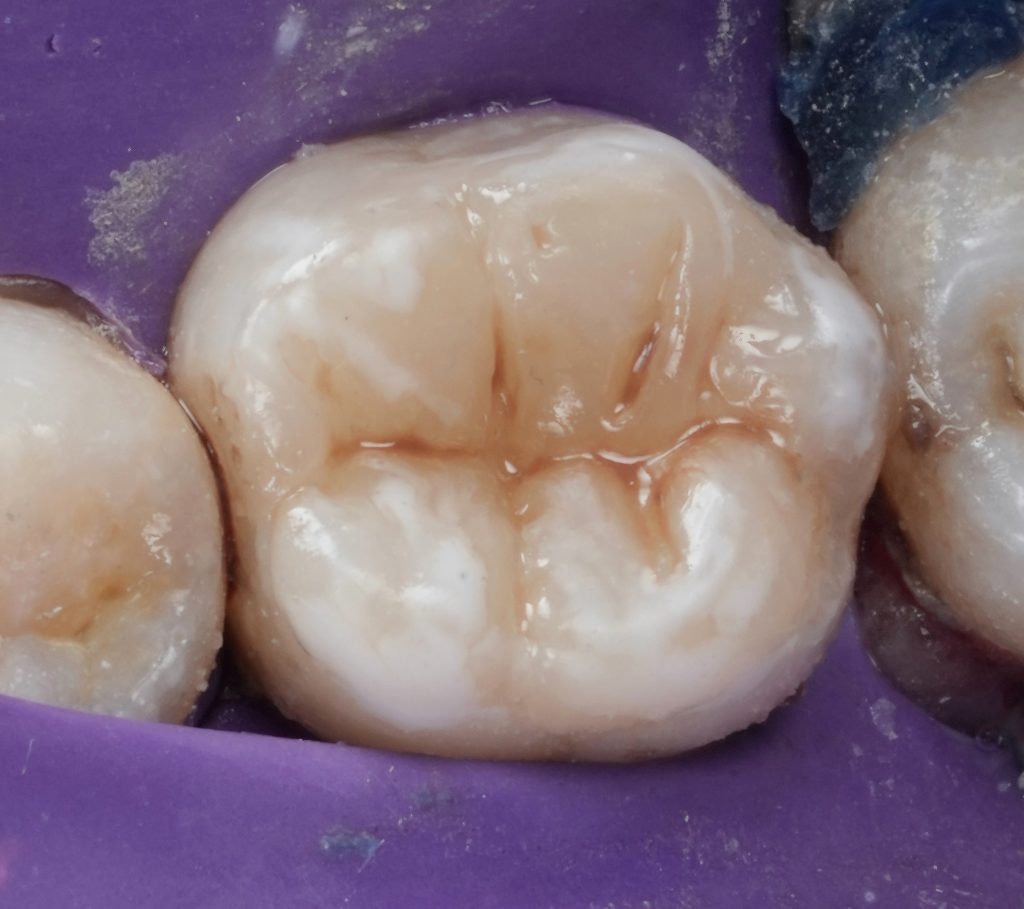

Clinical examination revealed a deeply carious mandibular first molar associated with pulpal pathology. Percussion sensitivity and radiographic findings confirmed the need for root canal treatment. The tooth exhibited weakened cusps due to caries and access requirements.

Given the extent of tooth structure loss and the functional demands on mandibular first molars, cuspal coverage was indicated. Occlusal anatomy was rebuilt using a biomimetic approach to restore:

- Functional cusp inclines

- Proper occlusal contacts

- Even stress distribution during mastication

Finishing and polishing were completed to achieve smooth margins and harmonious occlusion.